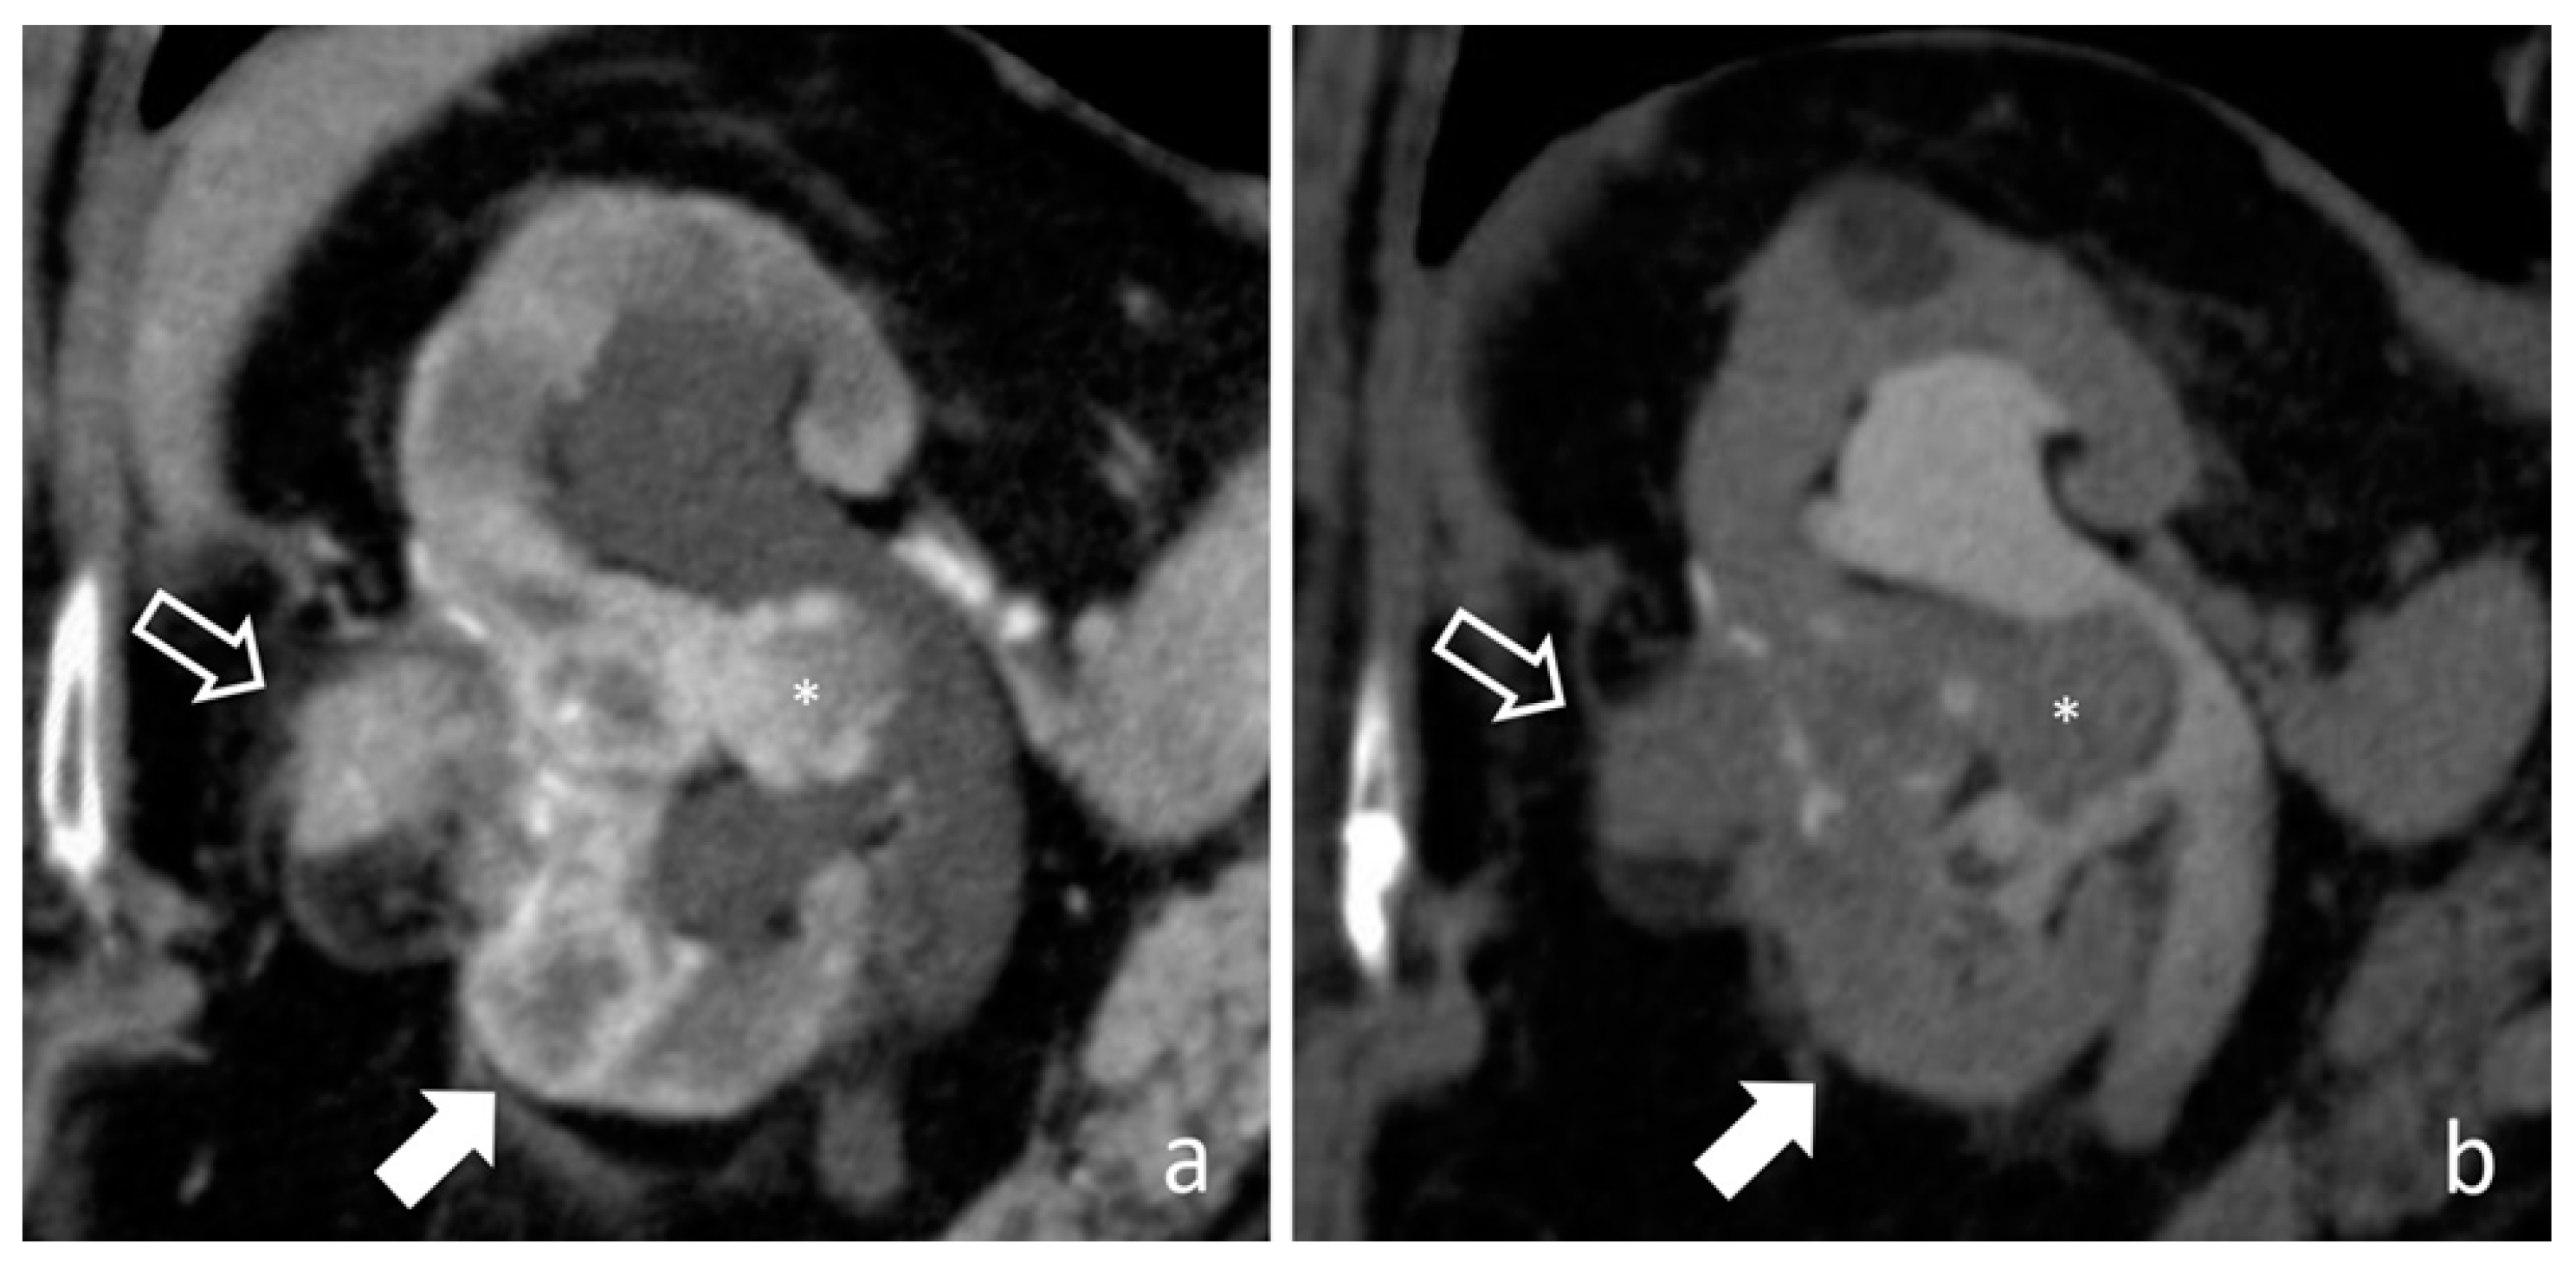

4.10. Renal Cell Carcinoma